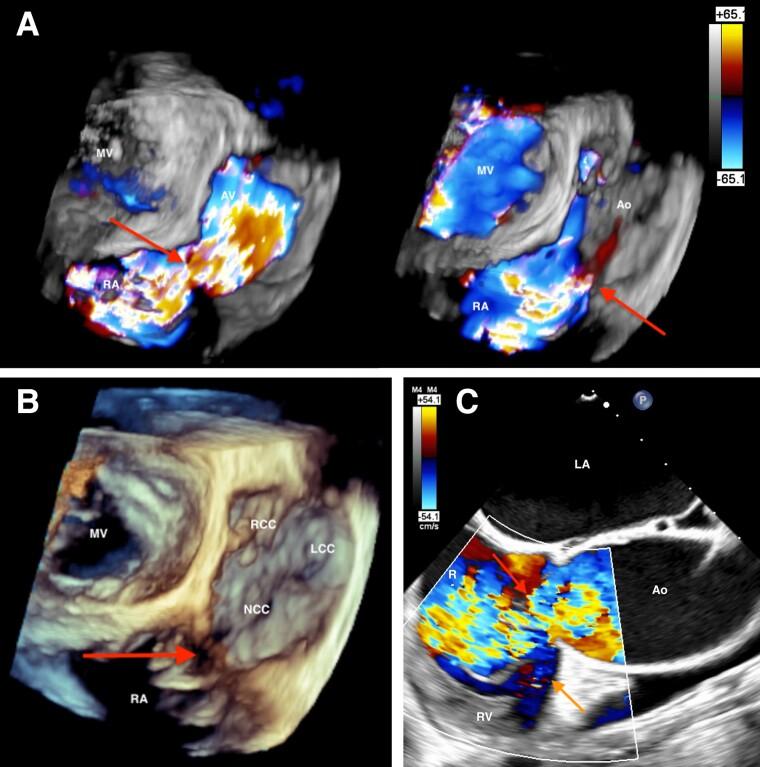

A multimodality approach to a rare case of ruptured sinus of Valsalva aneurysm with tricuspid valve involvement: a case report.

Ruptured sinus of Valsalva aneurysm is a rare disease entity that is potentially life-threatening if left untreated. While imaging is the mainstay of diagnosis, resultant tricuspid valve involvement may mask typical findings providing a diagnostic challenge. Disruption of the tricuspid valve during ruptured sinus of Valsalva aneurysm with consequent tricuspid regurgitation is rare and infrequently described in the literature. Description of the utility and limitations of multimodality imaging in this scenario is equally scarce.

We review the case of a young patient presenting with acute ruptured sinus of Valsalva aneurysm and involvement of the tricuspid valve on a background of severe aortic regurgitation requiring multimodality imaging for diagnostic and pre-surgical assessment.

In young patients presenting with acute decompensation and pre-existing bicuspid aortic valve regurgitation, an increased clinical suspicion of a sinus of Valsalva aneurysm rupture is imperative. Doppler and 3D transoesophageal echocardiographic assessment should be pursued to characterize abnormal flows and clarify aetiology in the context of tricuspid involvement and resultant tricuspid regurgitation. A large-volume left-right shunt in proximity to the tricuspid annulus may result in disproportionately severe tricuspid regurgitation in the absence of annular disruption due to forced systolic opening of the leaflets by shunt flow and 'windsock' prolapse. Multimodality imaging can be essential in these cases to adequately assess the extent of the ruptured sinus of Valsalva aneurysm and overcome limitations of single modality imaging.